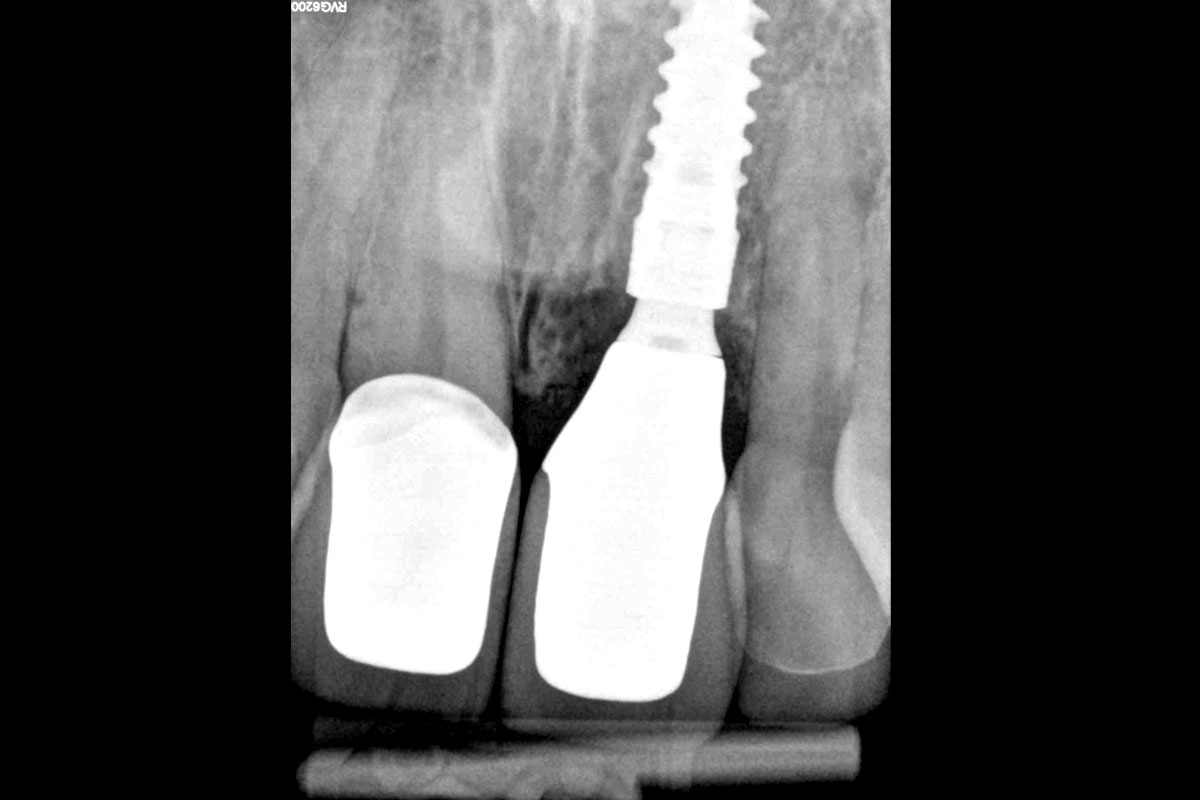

cerabone® and mucoderm® for immediate implantation in the aesthetic area - Dr. D. Robles

Initial clinical situation - Central incisors with dental destruction and periapical pathology